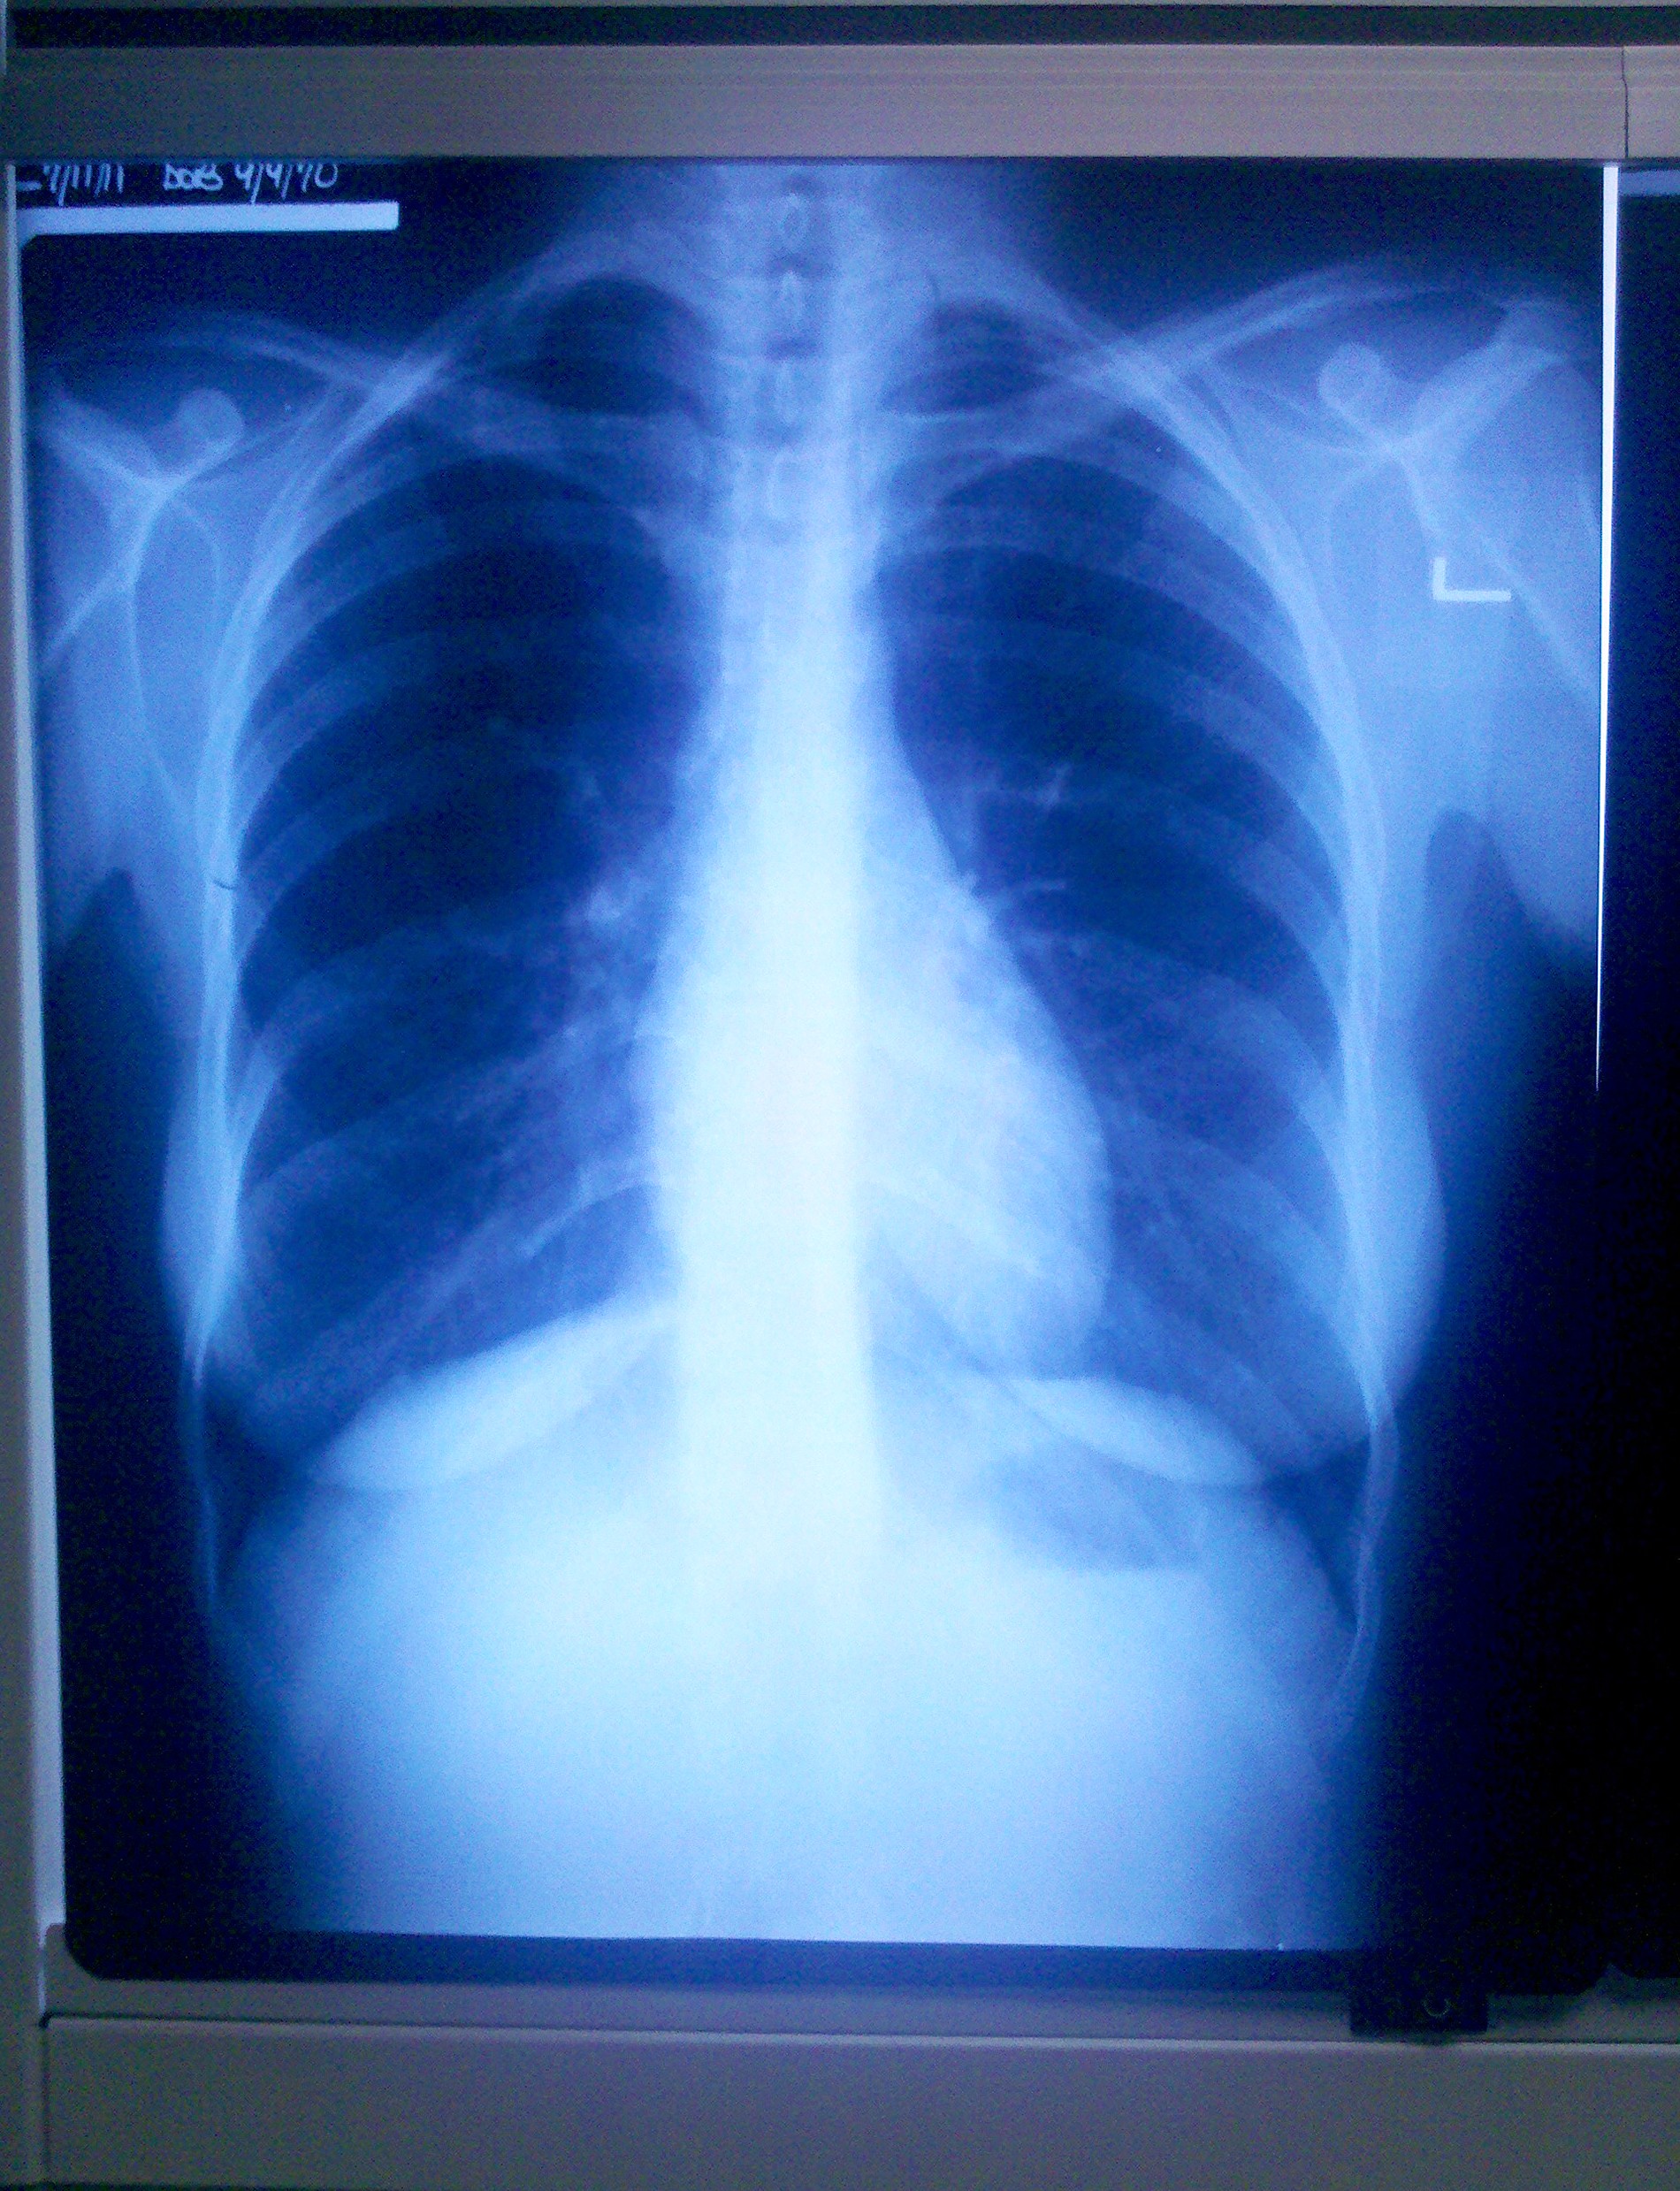

Have you ever seen an x-ray or other imaging of the inside of your body? It’s truly a thing of beauty. There’s something inherently magical about viewing your body’s parts and processes in their interconnectedness. Several years ago, I had to have an ultrasound done of my heart, and it was awe-inspiring to see my heart beating while I could feel it pumping away in my chest. The only thing that eclipsed it, of course, was seeing my daughter in the womb via 3D ultrasound. Anyway, I was able to take a picture of my lovely chest x-ray on the light box while the doctor was out of the room. (Glad I did too, because he drew all over it during his review, much to my horror.)

We have a tentative diagnosis of elevated hemidiaphragm. Basically, what that means is, one side of the diaphragm is higher than the other, which leaves less room for the lung to fully inflate. I still have to go for a “sniff test” (which sounds weirder than it is) where they view my lungs via fluoroscopy (can I get a copy of that too, please?) while doing forceful breathing to see if the diaphragm is not moving as it should. After that, we will know if it truly is elevated hemidiaphragm or we’re back at square one. My diaphragm is not severely elevated, which would probably require surgery. I asked what possible therapeutic options were recommended. He said to get a good heart rate monitor with the goal of raising my heart rate to recommended levels and to breathe slower during strenuous exercise.

Now, here’s where things get interesting. If I have elevated hemidiaphragm, how did I get it? One possible cause is damage to or impingement of the phrenic nerve, which controls the diaphragm. In most cases, it would require some form of trauma to cause injury to the nerve, which runs through the cervical spine. But as I was digging around the internet, I came across a reference to “nerve root impingement secondary to cervical spine degenerative disease.” I have congenital cervical spine stenosis, which has caused nerve impingement issues for nearly 20 years. Could it possibly be contributing to the pulmonary issues I’m experiencing – and have experienced for as long as I can remember with strenuous exercise? And if it isn’t elevated hemidiaphragm, then what is going on with me, because the test results clearly indicate some abnormal pulmonary functioning that is not explained by obstructive airway disease (and my lung x-ray was beautifully clear, as you can see.)

(P.S. That’s a picture of MY lungs there – please do not use it without permission!)